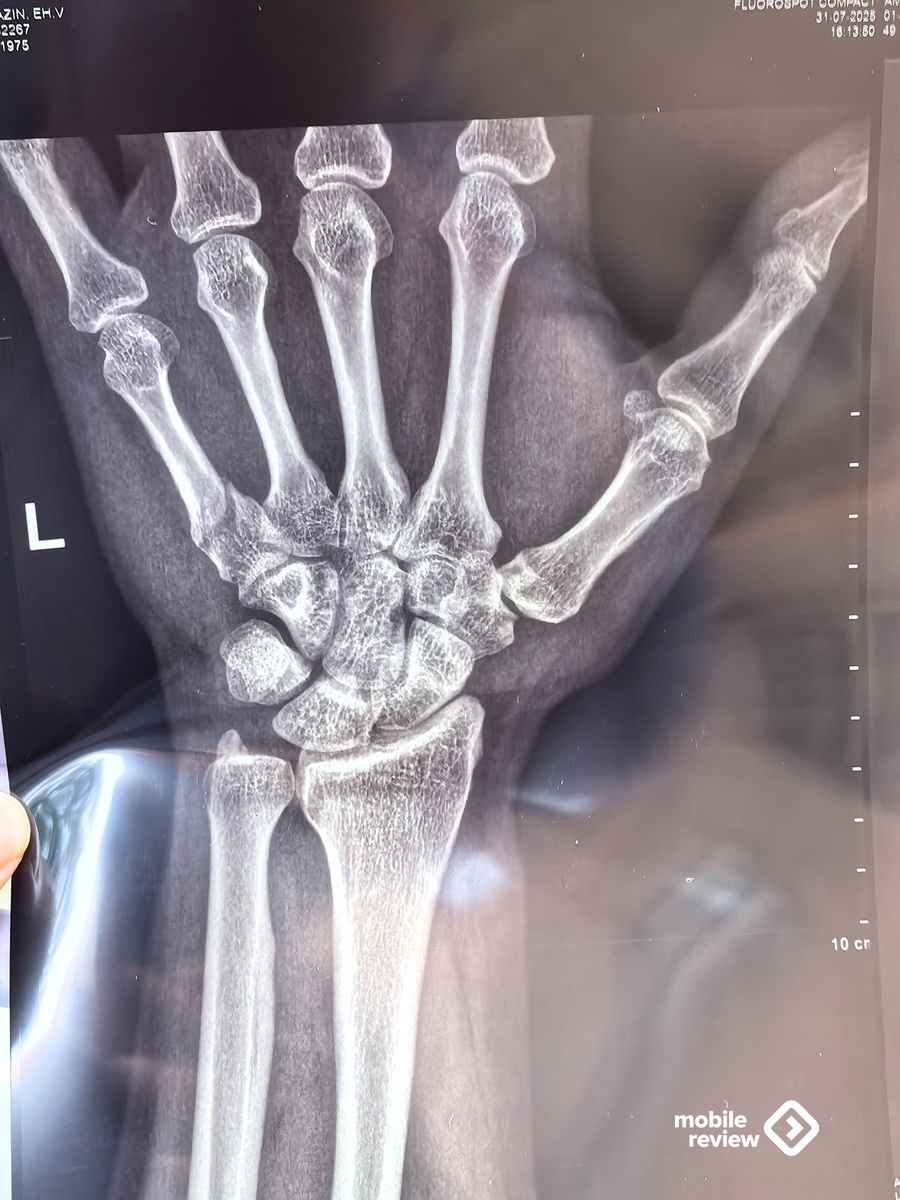

Московские пробки, в такси обзваниваю места вокруг, где мне могут сделать рентген, чтобы оценить степень повреждений. Пока ситуация 50 на 50, подвижность руки полная, но есть припухлость и болевые ощущения. После рентгена становится понятно: перелом и небольшое смещение.

Расписание уже полетело к чертям, но нужно попасть на презентацию от МТС, тем более что врач-травматолог примет меня только позже. Пообщался на презентации, успел даже подписать свою старую книгу для коллеги, показал снимок руки паре товарищей. Развлекался. После врача закончил вечер еще и тем, что провел почти часовой эфир, не стал его отменять. Насыщенный день.

До эфира был травматолог, обсуждение, что и как делать, отказался от восстановления эстетики, в будущем будет небольшая вмятина на руке. Поставили гипс на четыре недели, через неделю нужно снова идти на рентген и смотреть, как срастается кость.

Оставили несколько пальцев без гипса, посоветовали, как работать на компьютере и как точно не стоит, учусь жить заново в новых условиях. Жизнь с ограниченно доступной рукой довольно удивительна — совсем другие возможности и эмоции. Пишу этот текст на второй день с гипсом, ожидал, что все будет намного хуже. Тем не менее, рука елозит по клавиатуре, текст как-то набирается.